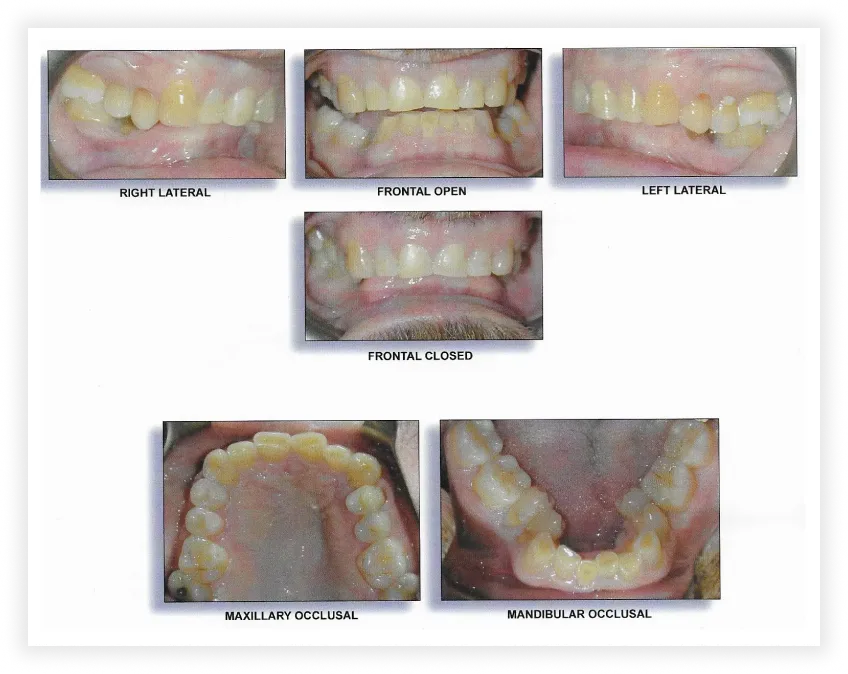

Final Photos